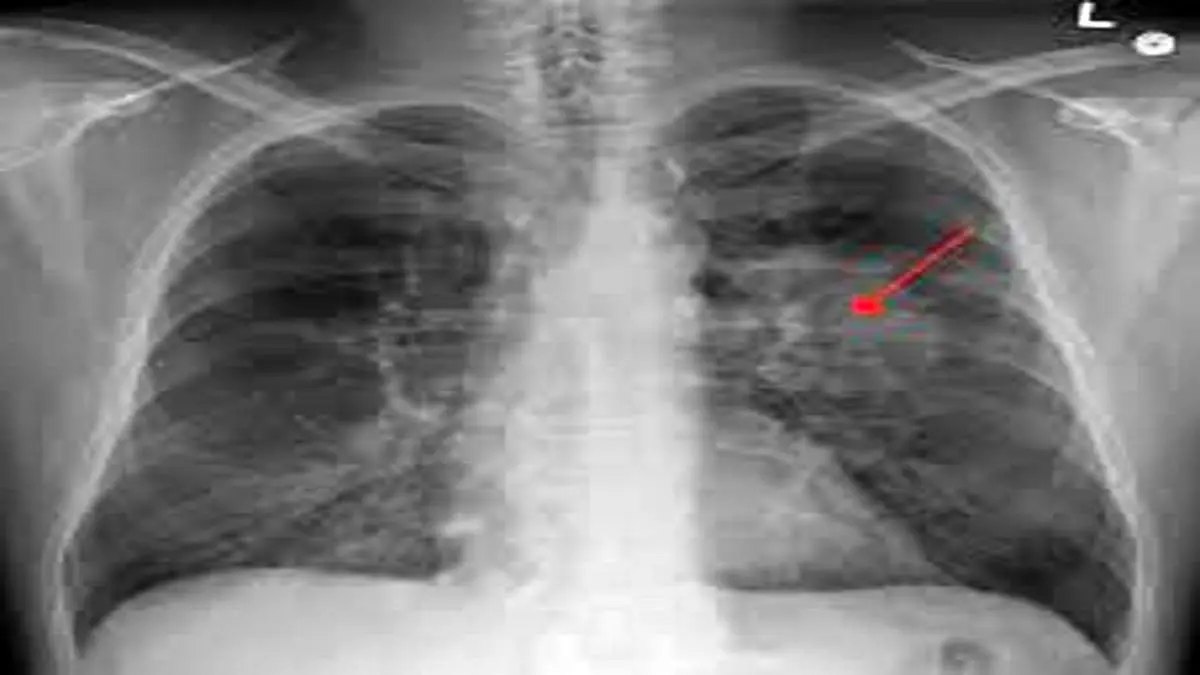

سرطان ریه یکی از عوامل اصلی مرگ و میر ناشی از سرطان در سراسر جهان است و سالانه بیش از دو میلیون نفر در جهان به این بیماری مبتلا میشوند. اکثر کسانی که دچار سرطان ریه میشوند سابقه مصرف سیگار دارند اما در حدود ۱۰ تا ۲۰ درصد مبتلایان هیچگاه سیگار نکشیدهاند. سرطان ریه در غیر سیگاریها بیشتر در زنان و در سنین پایینتر نسبت به سیگاریها رخ میدهد.

در این مطالعه بزرگ اپیدمولوژیک، محققان برای درک تغییرات ژنومی ایجاد شده در غدهها و بافت طبیعی، به توالی یابی کامل ژنوم ۲۳۲ فرد غیرسیگاری پرداختند. این افراد که عمدتا اروپایی تبار بودند به سرطان کارسینوم ریه سلول-غیرکوچک دچار شده بودند. این نوع سرطان که حدود ۸۰ تا ۸۵ درصد سرطانهای ریه را تشکیل میدهد شایعترین نوع سرطان در بین افراد غیر سیگاری است.

در این افراد ۱۸۹ تومور "آدنوکارسینوما" (adenocarcinomas) که شایع ترین نوع سرطان ریه است یافت شد. همچنین ۳۶ تومور کارسینوئید(carcinoids) و هفت نوع تومور از انواع مختلف دیگر در این بیماران دیده شد. بیمارانی که تحت بررسی قرار داشتند هنوز درمان خود را شروع نکرده بودند.